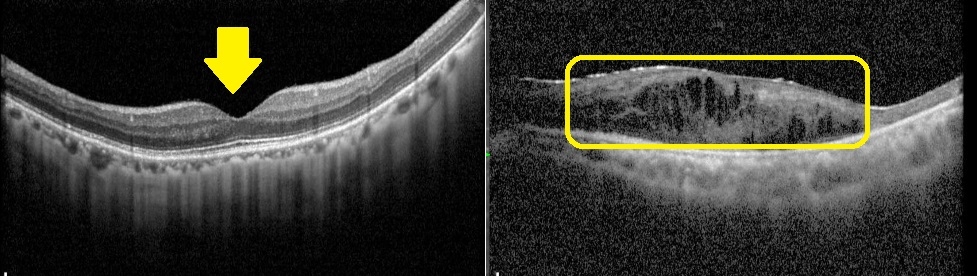

黃斑部病變分為乾性與濕性兩類,乾性病變約佔8成,病程進展慢,目前無特效藥,只能靠改善生活習慣延緩惡化,如配戴太陽眼鏡防止強光照射、戒菸、控制三高、補充抗氧化營養素等;濕性病變惡化速度快,主要是由新生血管異常增生造成出血與水腫,需透過眼內玻璃體注射抗血管新生藥物治療。若符合健保給付標準,單眼最多可施打14劑眼內注射藥物,臨床顯示約8成患者連續注射3劑後,3個月內視力可改善;但若延誤治療,95%的濕性患者在2年內可能造成失明,因此及早診斷與介入治療至關重要。